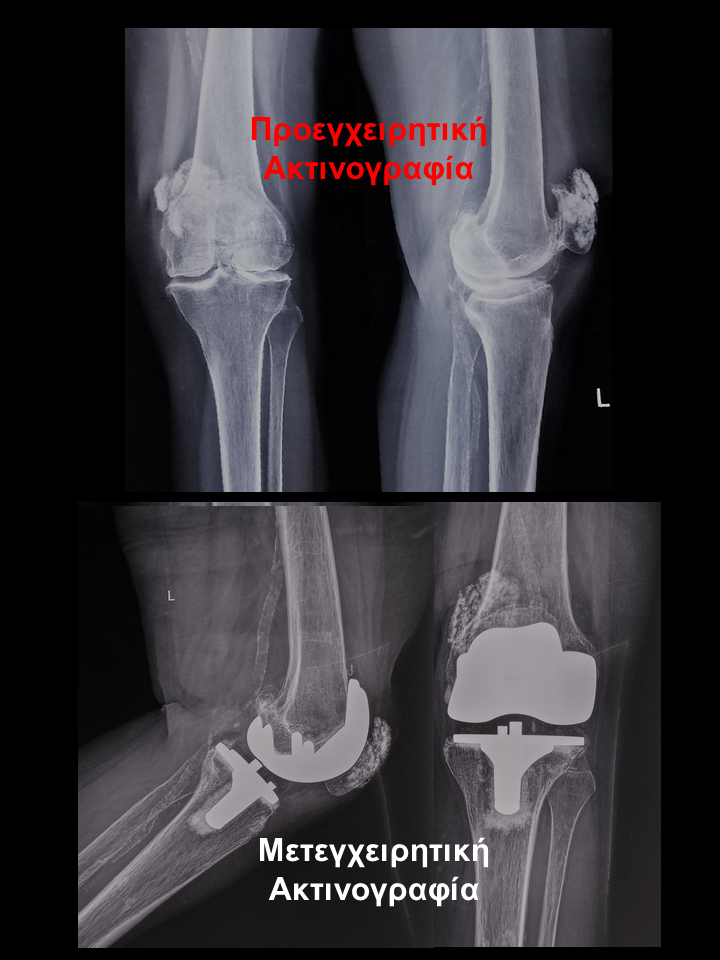

Ασθενής με οστεοαρθρίτιδα αριστερού γόνατος και μεγάλη παραμόρφωση

Ασθενής  80 χρονών με οστεοαρθρίτιδα αριστερού γόνατος, μεγάλη παραμόρφωση και επιδεινούμενο άλγος γόνατος που την δυσκόλευε στη βάδιση, στο κάθισμα και την αφυπνούσε το βράδυ. Υπεβλήθη σε ρομποτική αρθροπλαστική στο αριστερό γόνατο. Χρησιμοποιήθηκε η τεχνική διατήρησης οστού όπου αφαιρέθηκαν λιγότερα χιλιοστά οστού. Ο άξονας στο αριστερό γόνατο από 100 απόκλιση και έλλειμα έκτασης 50 αποκαταστάθηκε στις 00 . Η ασθενής βαδίζει πλέον χωρίς καμία ενόχληση.